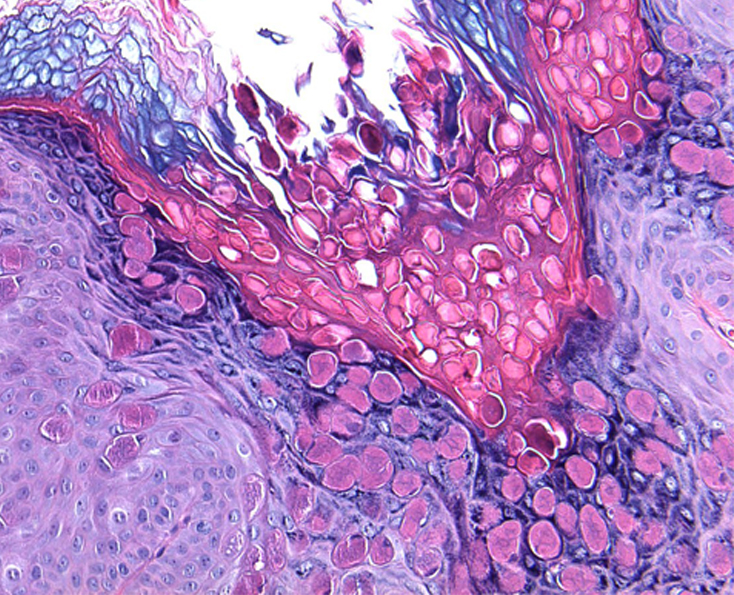

Клинические проявления неинфекционных заболеваний кожи при поражении аногенитальной области в целом не отличаются от таковых другой локализации. Однако целый ряд особенностей пораженной области – разная степень кератинизации эпителия, хорошая васкуляризация, окклюзия и мацерация кожным салом, потом и вагинальным отделяемым, высокий рH кожи (результат расщепления бактериальными уреазами мочевой кислоты с образованием аммиака), трение – нередко приводят к изменениям их клинической картины. Это существенно затрудняет распознавание заболеваний гениталий и перианальной области. Значительное сходство субъективной симптоматики и клинических проявлений дерматозы аногенитальной области имеют с инфекционными, а также предраковыми заболеваниями данной локализации, что нередко является одной из причин поздней диагностики дерматозов и предраков. Ситуация усложняется различием классификаций и терминов, используемых разными клиницистами (акушерами-гинекологами, урологами

дерматологами) и морфологами, что приводит к непониманию и затрудняет преемственность (комплексный подход) в ведении этих пациентов.

Лечение дерматозов аногенитальной локализации нередко представляет сложную задачу и требует междисциплинарного подхода. Основные подходы к лечению дерматозов данной локализации включают восстановление кожного барьера, назначение противовоспалительных препаратов, в частности топических глюкокортикостероидов и/или топических ингибиторов кальциневрина, реже – системных глюкокортикостероидов, ретиноидов, гидроксихлорохина или дапсона, ослабление субъективной симптоматики, профилактику и лечение вторичной инфекции. Отсутствие эффекта от противовоспалительной терапии требует исключения предраковых заболеваний вульвы и является показанием для диагностической биопсии

Отсутствие эффекта от противовоспалительной терапии требует исключения предраковых заболеваний вульвы и является показанием для диагностической биопсии.